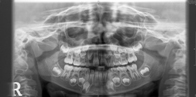

Radiographs (X-Rays) are taken to view areas which can not be seen on the surface of a tooth and to ultimately aid diagnosis and treatment planning. There are different types of xrays depending on what information is needed. Small xrays that the child bites on in the mouth help diagnose areas in between teeth.Larger X-Rays (OPG/Panorex) may be needed to assess the position and development of all adult teeth. Many times a cavity on a baby tooth may look small in the mouth, however with X-Rays the depth of the cavity can be seen which may be very deep and close to the nerve of the tooth. In some children, the teeth will look perfect in the mouth, but X-Rays will show areas of early decay which need to be monitored or restored.

X-Rays of front teeth (Anterior maxillary occlusal) may be needed after a child has sustained trauma to view the extent of the injury and impact on adult developing teeth.The decision to take X-Rays and which type, how often is based on the individual needs of a child. Good cooperation is needed for good quality X-Rays. The amount of radiation exposed is very low in dental X-Rays. All necessary precautions are taken to reduce the dose and equipment checked regularly.